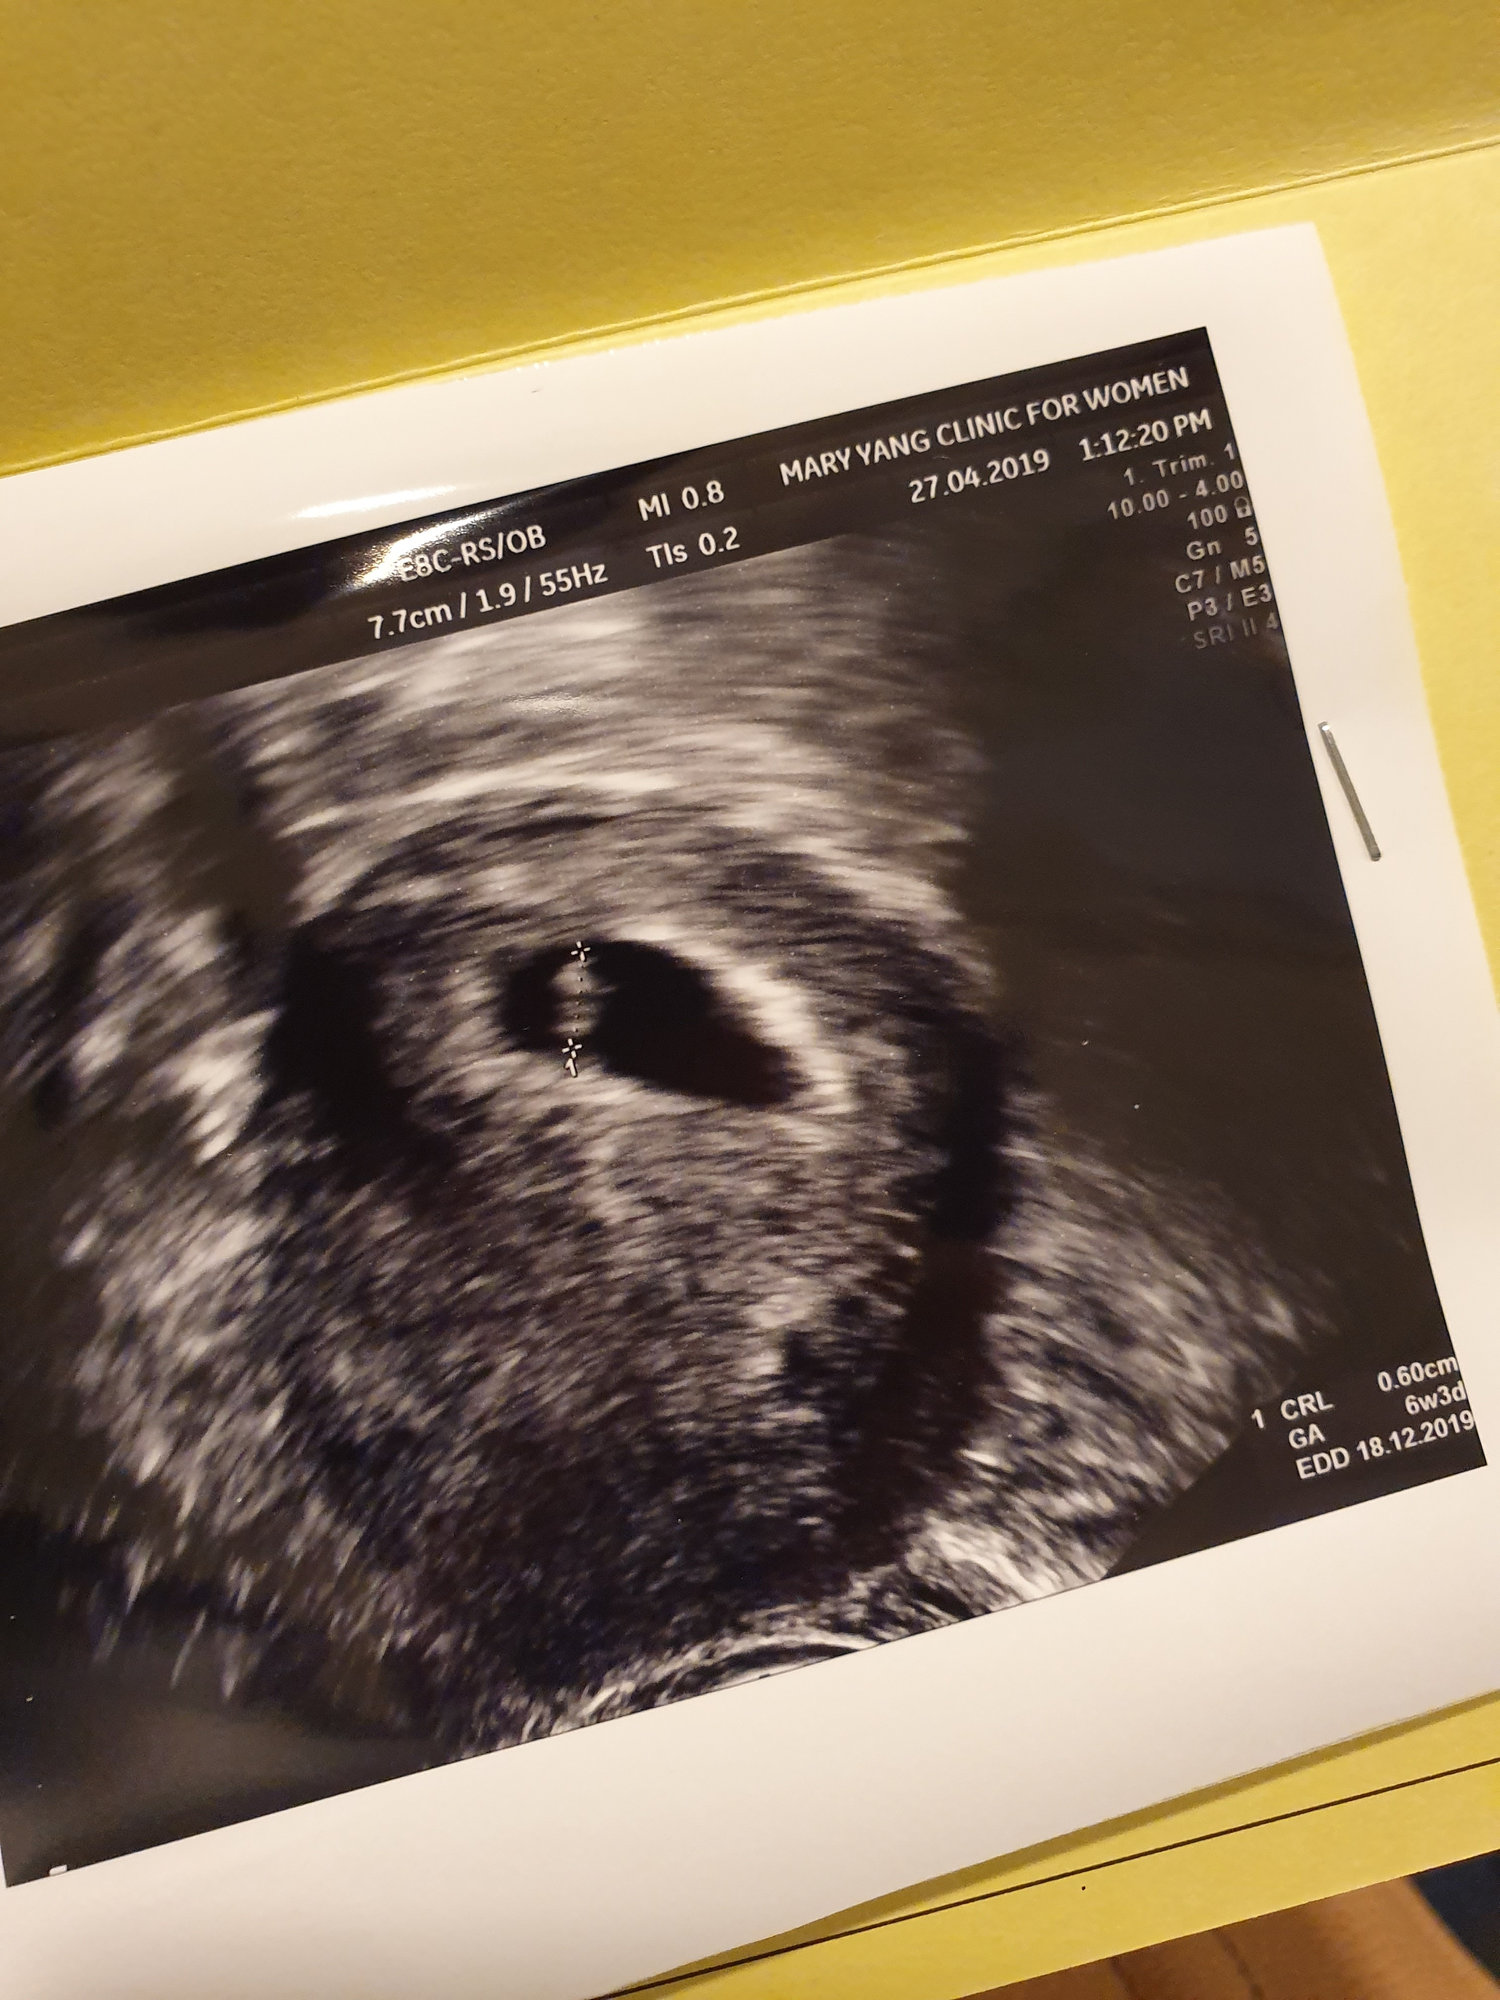

6w2d EDD 12/18!! HR 112

little bean (: